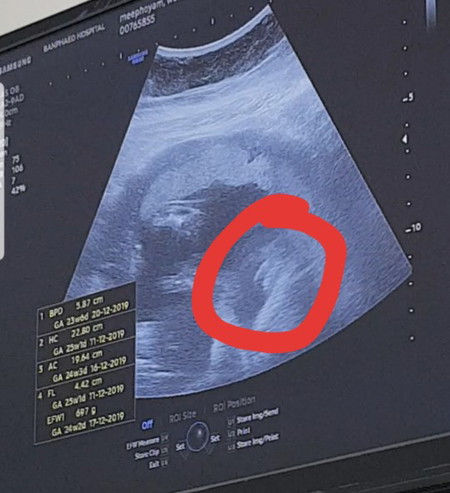

ใครรู้เพศแล้ว แบบนี้ ผญ หรือ ผช ค่ะ

ผญ นะคะคิดว่า ลูกเราก็เป็นงี้ หมอก็ว่าผญ

น่าจะผู้หญิงนะคะ เหมือนเห็นเป็นกลีบ